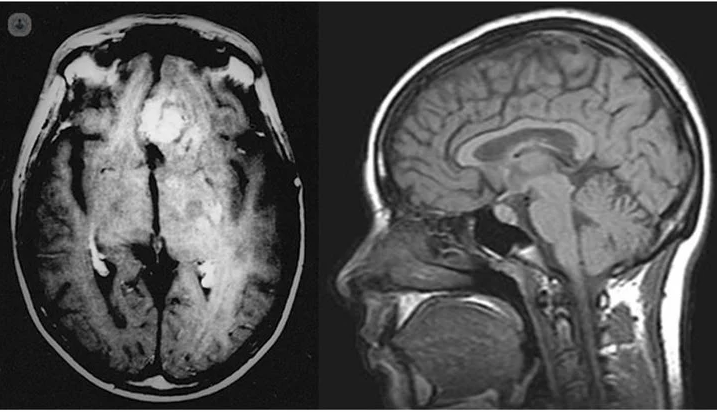

Una noche se le sumó vómitos, lo que causó que el médico de turno que lo vio le dijera que no iba a volver a casa. Le hicieron una tomografía y el diagnóstico fue devastador: un tumor cerebral. Estaba tan avanzado que le confirmaron que estaba a días de entrar en un coma debido al tamaño del mismo, por lo que tuvo que atravesar una cirugía de urgencia donde le extirparon el 70% del tumor.